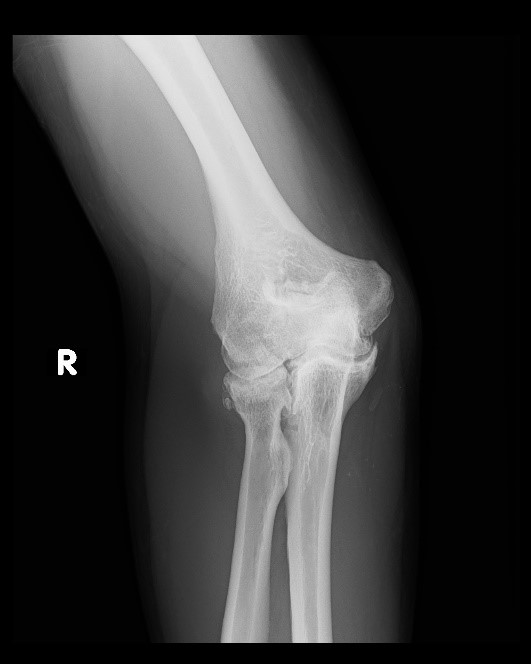

From thejointinjectionclinic.com

Elbow Arthritis Causes, Symptoms and Treatments Options Can Elbow Arthritis Be Cured Read on to learn more about what you can do to help manage pain caused by arthritis in elbows, including exercises from hinge health physical therapists so you can. The first treatments used for elbow arthritis include: Find out when to see a doctor and what exercises can help prevent or. There is no cure for osteoarthritis of the elbow,. Can Elbow Arthritis Be Cured.

Elbow Arthritis Causes, Symptoms and Treatments Options Can Elbow Arthritis Be Cured It could be elbow arthritis. How is arthritis of the elbow treated? If you have previously broken a bone at the elbow, it can increase the chance of developing osteoarthritis in the joint. Learn about the causes, symptoms, and treatment options for osteoarthritis of the elbow, a condition that affects the cartilage and joint surfaces of the elbow. Read on. Can Elbow Arthritis Be Cured.